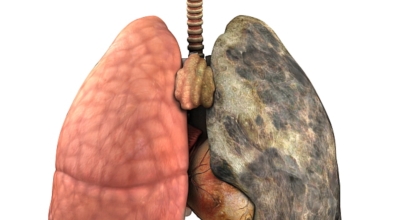

폐에 발생된 악성 종양을 말하며 오랜 기간 흡연해온 남성들에서 발병률이 높고 요즈음 각종 환경적인 요인의 영향과 간접흡연으로 흡연하지 않는 여성에서도 많이 발생하고 있습니다. 증상을 느껴 병원을 찾았을 때는 수술하기 늦은 경우가 많아 사망 가능성이 매우 높은 암입니다. 폐 자체에서 발생하거나 다른 장기에서 발생된 암이 폐로 전이되어 발생하기도 하고 특별한 초기 증상이 없는 경우가 많고 암이 진행된 후에도 공통적인 감기 증상인 기침과 가래 외의 특이 증상이 나타나지않아 증상만으로는 진단이 쉽지 않습니다.